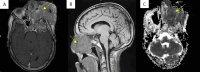

Chondrosarcomas represent 20%-30% of primary malignant bone tumors, but only about 1% occur in the head and neck region. Maxillary chondrosarcomas constitute a mere 5.76% of head and neck cases, predominantly affecting adults between the second and sixth decades of life. Symptoms, including facial swelling, pain, and nasal obstruction, often lead to delayed diagnoses and increased tumor aggressiveness. This case report details a 45-year-old Moroccan male with an aggressive maxillary chondrosarcoma presenting as a progressive left cheek swelling accompanied by significant pain and vision impairment. Imaging studies revealed a large, lytic maxillary lesion, and biopsy confirmed a low-grade chondrosarcoma. Given the tumor's unresectability, the patient underwent radiotherapy, receiving a total dose of 70 Gy with modest reduction in tumor size but ultimately developed metastatic pulmonary lesions, leading to palliative chemotherapy. Despite aggressive management, the patient succumbed after the fourth cycle of chemotherapy. This case underscores the importance of timely diagnosis and multidisciplinary collaboration in managing maxillary chondrosarcomas, highlighting the challenges posed by their aggressive nature and the need for long-term surveillance to monitor for recurrence and metastasis.